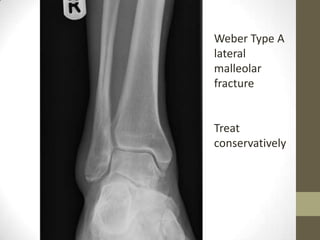

Weber Type A

lateral

malleolar

fracture

Treat

conservatively